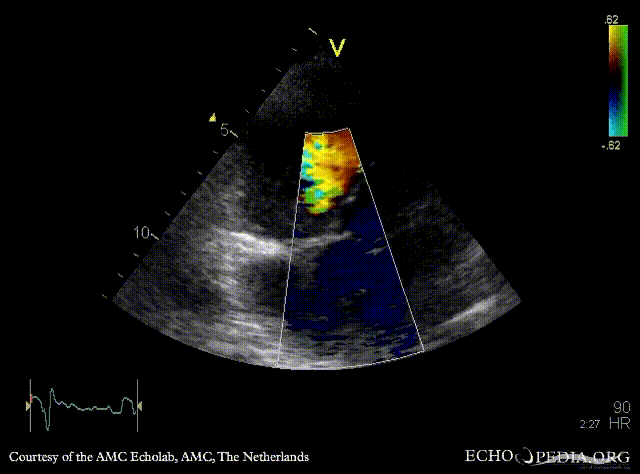

| A5CH: muscular VSD